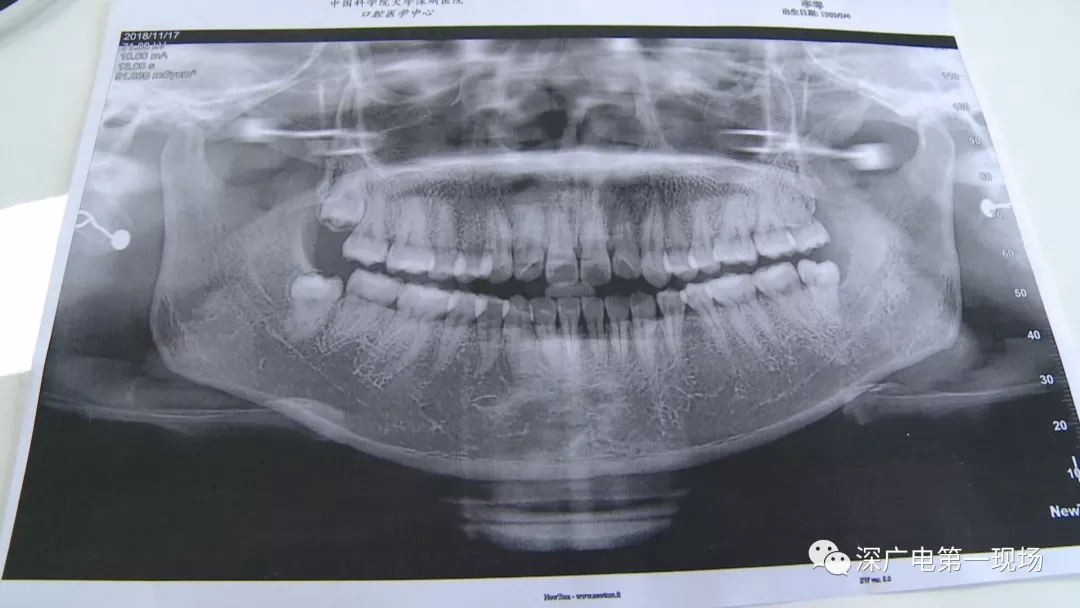

針對(duì)李女士的情況,醫(yī)生介紹,當(dāng)時(shí)要想拔出李女士的這顆智齒,難度還是很大的,屬于復(fù)雜智齒的拔除術(shù)。她的風(fēng)險(xiǎn)在于距離神經(jīng)管近,同時(shí)這顆牙齒完全埋在牙床最后的位置,直接往外拔,會(huì)加大頜骨的風(fēng)險(xiǎn),因此需要先切開,讓牙齒暴露后,切小再慢慢地拔出。